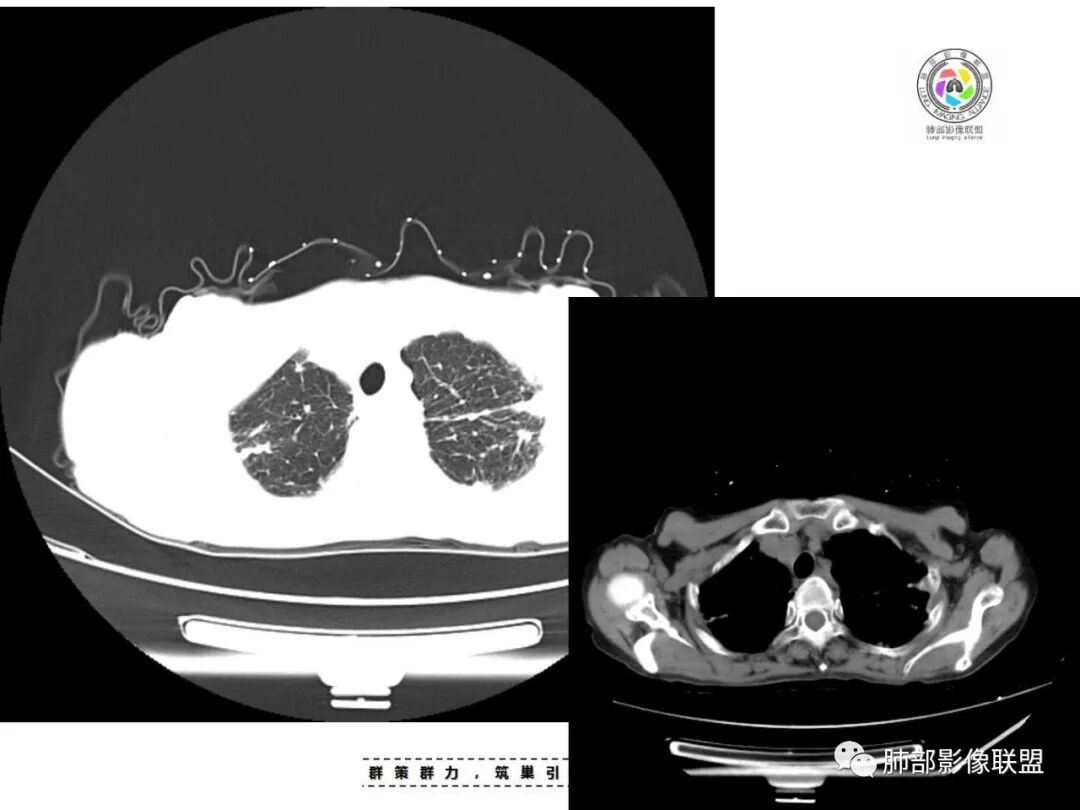

老年女性,67岁,咳嗽、咳痰半月余。双肺可闻及痰鸣音。

胸部CT:双肺上叶多发小结节,沿胸膜下、支气管血管束分布。右上肺斑片实变影、索条影及小叶间隔不均匀增厚,支气管枯枝征?纵隔淋巴结多发肿大,部分有钙化。综合考虑:结节病?尘肺?鉴别:腺癌并癌淋。

双侧胸膜下去多发结节状及斑片状实变影,周围伴有条索影,部分结节融合成小片状,中轴间质及小叶间隔增厚,纵隔淋巴结钙化,常规考虑结核,不除外合并尘肺。

支气管血管束是增厚的,多发病灶及纤维灶,有钙化及纵隔钙化淋巴结,树芽征,支持结核合并其他感染。

患者老年女性,亚急性起病,主要症状表现为咳嗽、咳痰半月余,查体:双现呼吸音粗,双肺可闻及痰鸣音。胸部CT:双上肺胸膜下可见多发小叶实变影,双上肺可见多发小叶中心性结节及小叶间隔增厚,右上肺后段可见亚段性实变影,内见多发空洞,前段可见GGO及树芽征,后段局部支气管闭塞,肺门淋巴结肿大并钙化。病灶整体:有气道、间质播散,一元论考虑肺结核合并支气管结核可能性大,建议好好查痰;这样病灶:明显实变+空洞+气道播散,若是结核,痰涂片找到抗酸杆菌应该没问题。建议支气管镜检查助诊,了解有无支气管结核及合并腺癌的可能。

*小结节,直径2-5mm,边缘清楚或不清楚,小叶中心性和胸膜下。

*弥漫分布,以上叶和后部为主,

*融合团块,形态不规则,含坏死区。

*局灶性小叶中心性肺气肿。

*不规则型或瘢痕型肺气肿。

*淋巴结肿大和钙化。

1.双肺片状影、大小不等斑片影、结节影、树芽等,病灶密度偏高多钙化。

2.病灶上肺为主,胸膜下分布为主。双肺病灶明显不对称,右肺块状影较大。

1.胸膜下为主,簇状分布,大小不等,新旧不等,树芽,密度偏高等等都结核病变影像学特点。

2.多数尘肺结节影相对比较随机,没有胸膜下分布优势。

尘肺结节显得“游离”、清晰,一般较为均匀,很少呈多形性、斑片、树芽或新旧不等改变,晚期形成的纤维块状影多是双上肺中带对称分布,也很少纵隔偏移。